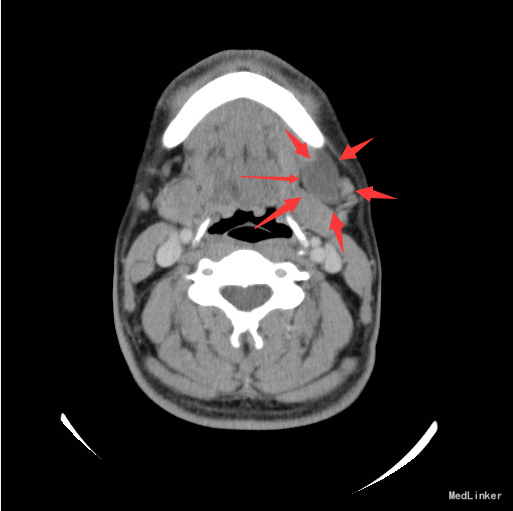

查体:左颌下可触及一肿物,大小约6*3cm,质软,无压痛,与周围组织境界不清。 辅查:颈部螺旋CT:左侧颌下三角区良性囊性肿块,考虑腮裂囊肿可能性大。

诊断:腮裂囊肿 治疗:排除手术禁忌,于全麻下行左颈深部肿物切除+颌下腺及舌下腺切除+颌下淋巴清扫术。术程顺利,术后予以消肿止痛、改善循环、预防感染等治疗,恢复满意。

随访:病理:(颌下及颏下肿物)组织内见一囊肿,囊壁由肉芽组织构成,未见内衬上皮,内含粘液,考虑为粘液囊肿。 讨论:鳃裂囊肿是由胚胎发育中鳃裂残余上皮组织发生的一种先天畸形。胚胎第4周1~4对鳃弓形成,鳃弓之间的腔隙为鳃裂,在胚胎第9周闭 合,如不闭合,残余上皮组织形成鳃裂囊肿。以第二鳃裂囊肿最为常见,约占90%。发生部位依次为耳、腮腺周围;颌下腺外侧、颈动脉间隙外侧、胸锁乳突肌前内侧、上颈后三角区、中、下颈沿胸锁乳突肌前缘,CT表现为沿胸锁乳突肌走行的圆形或类圆形囊性肿块,边界清晰,形态规则。伴有感染时囊壁增厚,边界不清,增强扫描囊壁明显强化。